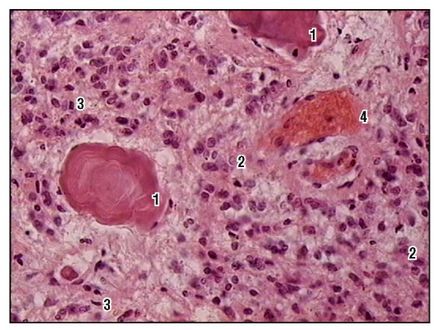

Fig. 163. Epifize (colorare cu hematoxilină și eozină, o creștere mare): 1 - concreții epifize (nisip cerebral); 2 - pinealocite; 3 - celule gliale interstițiale; 4 - vasele de sânge